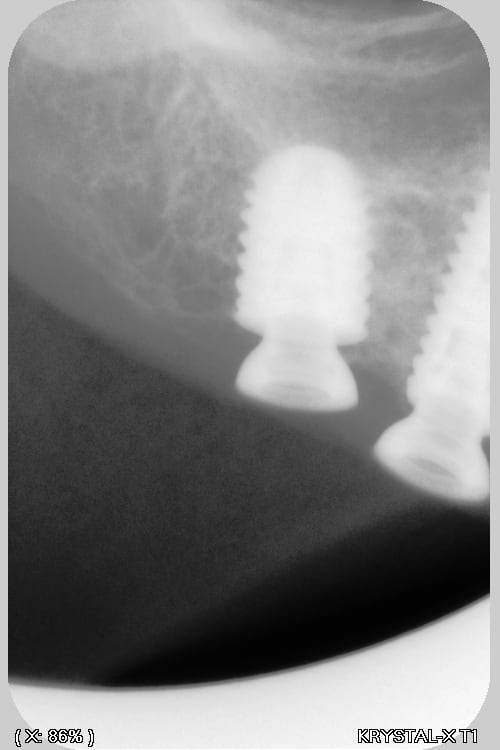

Si tu peux me donner la marque, et le type ça a été posé à Paris (2018?) Dentiste DCD, papiers perdu patiente 85 ans, adressé par un confrère qui pensait à des anthofit, mais ....

Bah, tu fatigues pxav? c'est pas des axiom reg avec ces piliers miltiunits comme ceux des TL????

Ces implants donnent le mal de mer !!! (cf pano !)

au départ je cherchais des Antogyrs , mais mon hésitation, est due au fait que (malgré mon stock de clé) je n'ai rien trouvé pour dévisser le multi unit...Bizarre, vous avez dit bizarre

C'est de l'Anthogyr avec des piliers InLink

Il faut utiliser le tournevis Anthogyr pour accès angulé (tête boule)

Effectivement, c'est le seul truc que je n'utilise pas chez eux...c'est très ingénieux, mais dans le cas présenté, ils ont tous cassés..., j'attends de voir la prothèse d'origine pour savoir d'où vient le soucis.